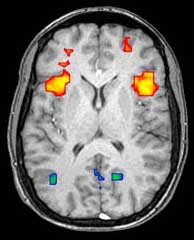

Axial MRI slice at the level of the basal ganglia, showing fMRI BOLD signal changes overlayed in red (increase) and blue (decrease) tones.